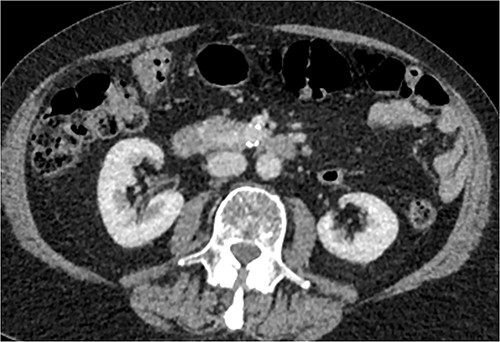

A multiphase CT of the pancreas had unexpected findings. There were no pancreatic masses on the arterial and portal phase study, and no paraaortic or mesenteric lymphadenopathy. The abnormal calcification seen on the previous study corresponded to a dilated vessel along the superior margin of the pancreatic body. This dilated vessel was an abnormal communication between a tortuous ecstatic gastroduodenal artery and the first branch of the SMA, a Buhler’s arc communication. The celiac axis origin was narrowed >90%. No other suspicious solid organ mass lesion was identified. Soft tissues were unremarkable (Figs 5–8).

Multiphase CT pancreas, axial view demonstrating abnormal communication between the CA and the SMA.